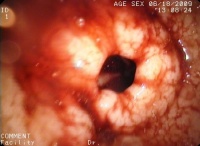

食管炎胃镜

把防止胃食管的反流。贲门部食管入口处的黏膜聚拢多及食管下的高压区亦均为防止反流的重要因素。这些正常解剖关系均起着防止胃食管反流的作用。破坏了防止胃食管反流机制,食管胃接合部闭合不全就会导致频繁反流。